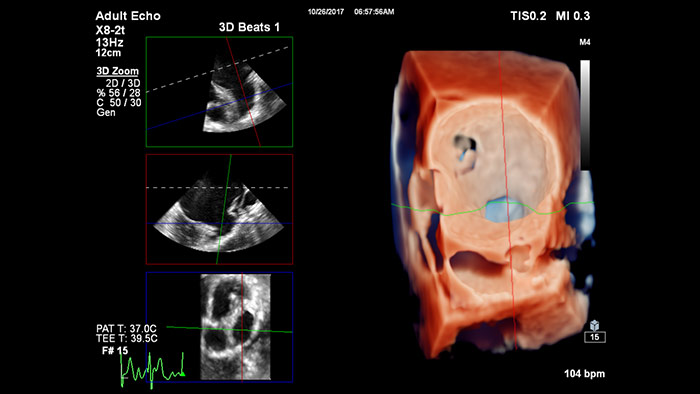

Segmentación del modelo EchoNavigator 3D

Reproducción con TrueVue con zoom 3D para LAA con visualización MultiVue